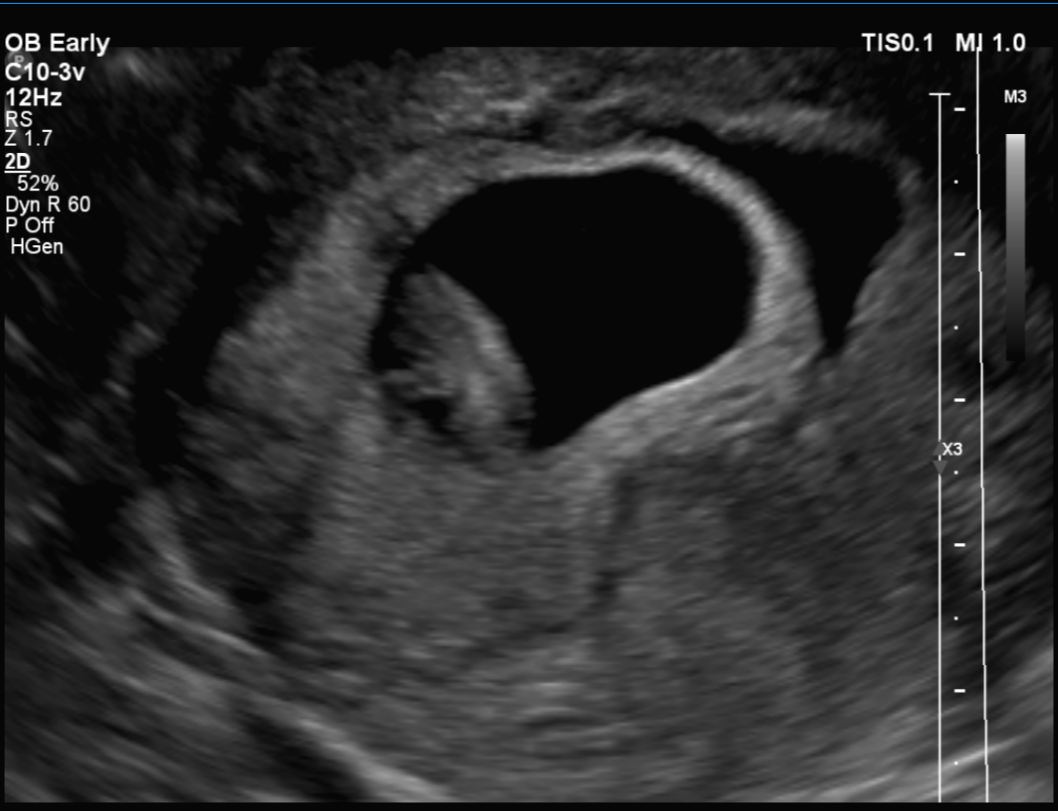

임신 8주 차 초음파 검사 ( 8주 5일 차 초음파 사진)

첫 트롱이 사진 짜잔~~ 젤리곰 이다 >. < 주수에 맞게 잘 자라고 있는 트롱이~ 심박수도 176 bpm으로 정상!

사실 초음파 검사 당시엔 아기 모습을 보지 못했어요~ 검사해주는 분께서 화면으로 보여주지도 않고 아무 말 없이 혼자 보면서 검사를 하시더라고요~ 그래서 저희 남편만 화면으로 확인하면서 너무 귀엽다고 잘 자라고 있다고 ㅠㅠ 저를 안심시켜줬습니다.

검사가 끝나고 전 메일로 받은 초음파 사진으로 처음 우리 아이를 봤어요~! 보고 나서 너무 귀엽고 제 뱃속에 이 작은 생명이 있다는 게 너무 신기해서 울었어요~ ㅜ.ㅜ~ ㅋㅋㅋ